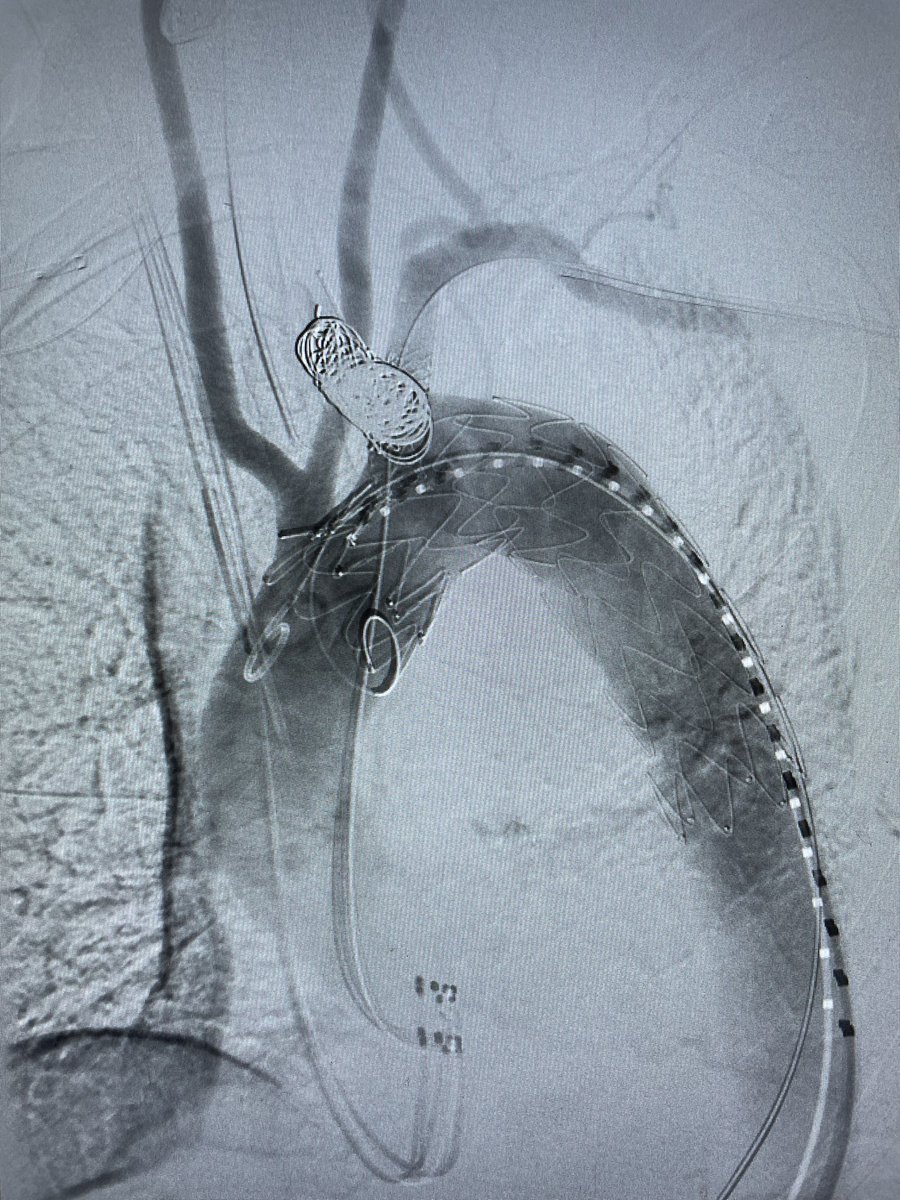

Young man with chronic TBAD with new pain & high risk features - treated with L carotid-subclavian bypass and Zone II TEVAR and LSA Amplatzer 🤙🏼 Rameen S. Moridzadeh, MD Vascular Surgery Associates Cedars-Sinai Division of Vascular Surgery #VascSurg #VascularTwitter #SoMe4Surgery #MedEd #aortaed